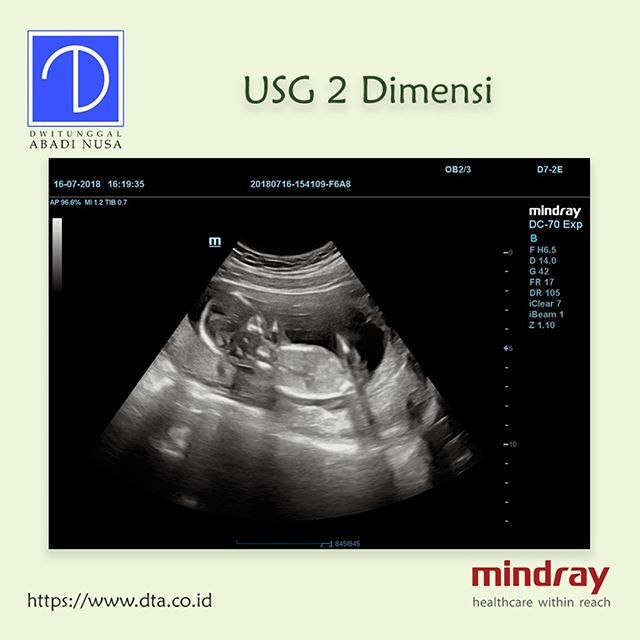

Dwitunggal Abadi Nusa On Twitter Contoh Hasil Usg 2 Dimensi Usg2d Usg2dimensi Usg Hasilusg Usgmindray Mindray Mindrayindonesia Healthcare Medical Dc70exp Dc70expert Dtamedika Https T Co Lwrm6xjjae

Dwitunggal Abadi Nusa On Twitter Contoh Hasil Usg 2 Dimensi Usg2d Usg2dimensi Usg Hasilusg Usgmindray Mindray Mindrayindonesia Healthcare Medical Dc70exp Dc70expert Dtamedika Https T Co Lwrm6xjjae

Dwitunggal Abadi Nusa On Twitter Contoh Hasil Usg 2 Dimensi Usg2d Usg2dimensi Usg Hasilusg Usgmindray Mindray Mindrayindonesia Healthcare Medical Dc70exp Dc70expert Dtamedika Https T Co Lwrm6xjjae

Dwitunggal Abadi Nusa On Twitter Contoh Hasil Usg 2 Dimensi Usg2d Usg2dimensi Usg Hasilusg Usgmindray Mindray Mindrayindonesia Healthcare Medical Dc70exp Dc70expert Dtamedika Https T Co Lwrm6xjjae

Dwitunggal Abadi Nusa On Twitter Contoh Hasil Usg 2 Dimensi Usg2d Usg2dimensi Usg Hasilusg Usgmindray Mindray Mindrayindonesia Healthcare Medical Dc70exp Dc70expert Dtamedika Https T Co Lwrm6xjjae

Dwitunggal Abadi Nusa On Twitter Contoh Hasil Usg 2 Dimensi Usg2d Usg2dimensi Usg Hasilusg Usgmindray Mindray Mindrayindonesia Healthcare Medical Dc70exp Dc70expert Dtamedika Https T Co Lwrm6xjjae